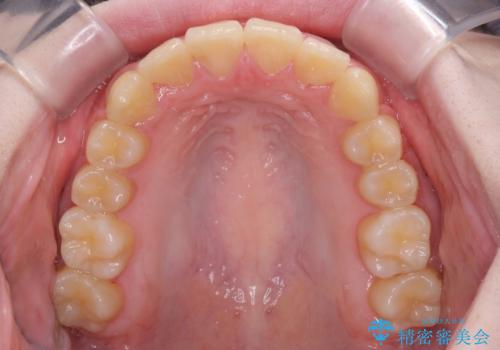

治療途中で大学受験があり、来院できない時期がありましたが、2年以内で満足のいく歯並びを達成することができました。